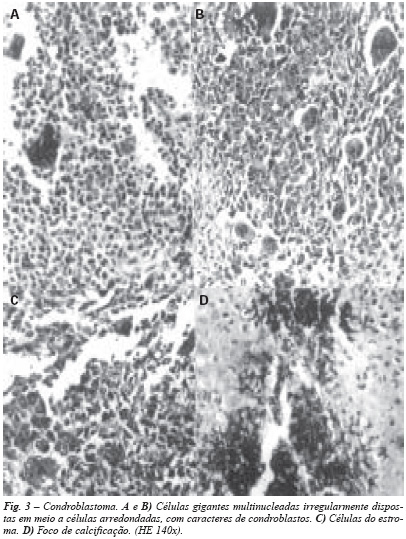

Condroblastoma: neoplasia própria da segunda década da vida, em epífise de óssos longos, mais freqüente na extremidade proximal do úmero, distal do fêmur e proximal da tíbia.

É a neoplasia que histologicamente mais se assemelha ao tumor gigantocelular, do qual foi descartado por Codman(22), que a designou "tumor gigantocelular epifisário calcificado". Predominam células gigantes multinucleadas em meio a estroma de células arredondadas com caracteres de condroblastos, com áreas onde há produção de tecido cartilaginoso e focos irregulares de calcificação, que no início contorna restos de células do estroma, assumindo o chamado aspecto de "calcificação em tela de galinheiro" (fig. 3).